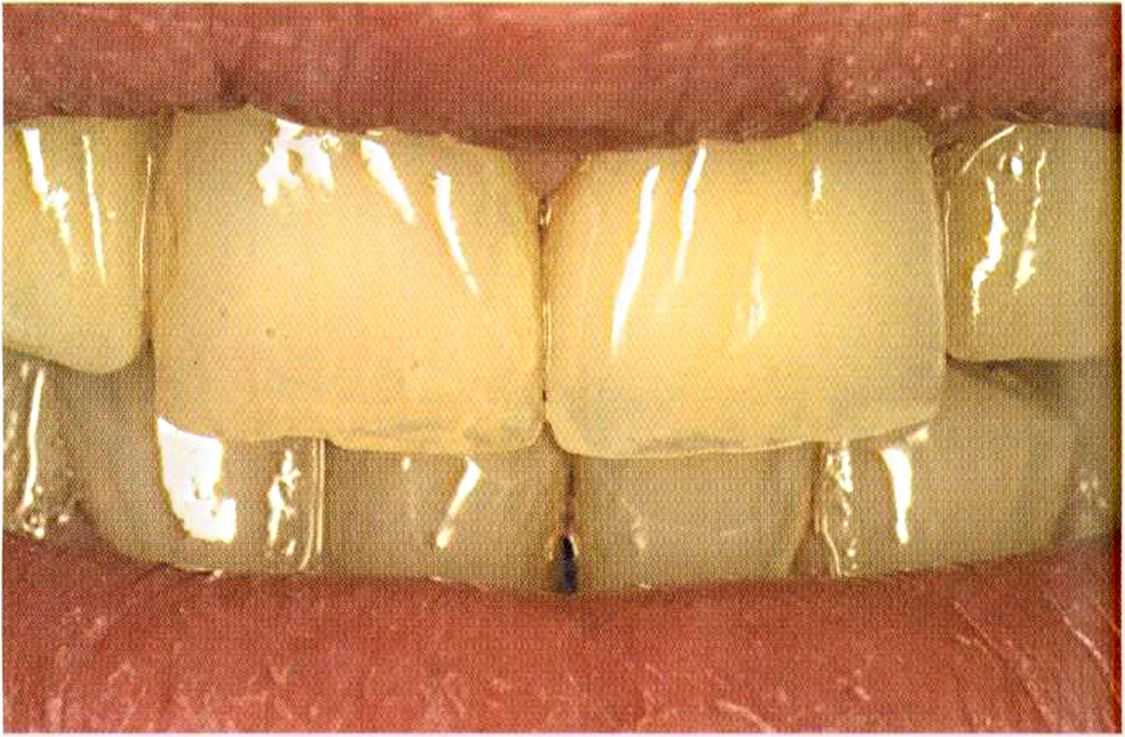

Зафиксированные на цемент коронки в полости рта. Видны излишки цемента, которые потом легко удалить, они отскакивают, как яичная скорлупа.

После обработки Tubulitec на культях возникает белая пленка.

Излишки удалены.